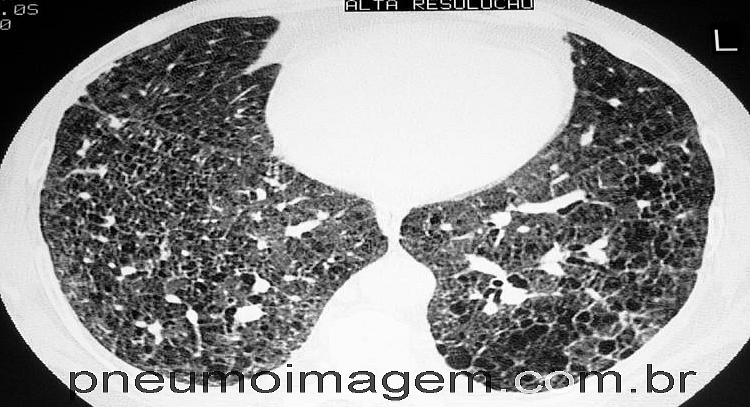

CONSULTA PÚBLICA PARA INCORPORAR MEDICAÇÃO PARA FIBROSE PULMONAR IDIOPÁTICA NO SUSA Comissão Nacional de Incorporação de Tecnologias no SUS (CONITEC) dispõe sobre a assistência terapêutica e a incorporação de tecnologia em saúde no Sistema Único de Saúde (SUS). A CONITEC fez uma recomendação preliminar para a não incorporação do nintedanibe para o tratamento da Fibrose Pulmonar Idiopática (FPI) no SUS.